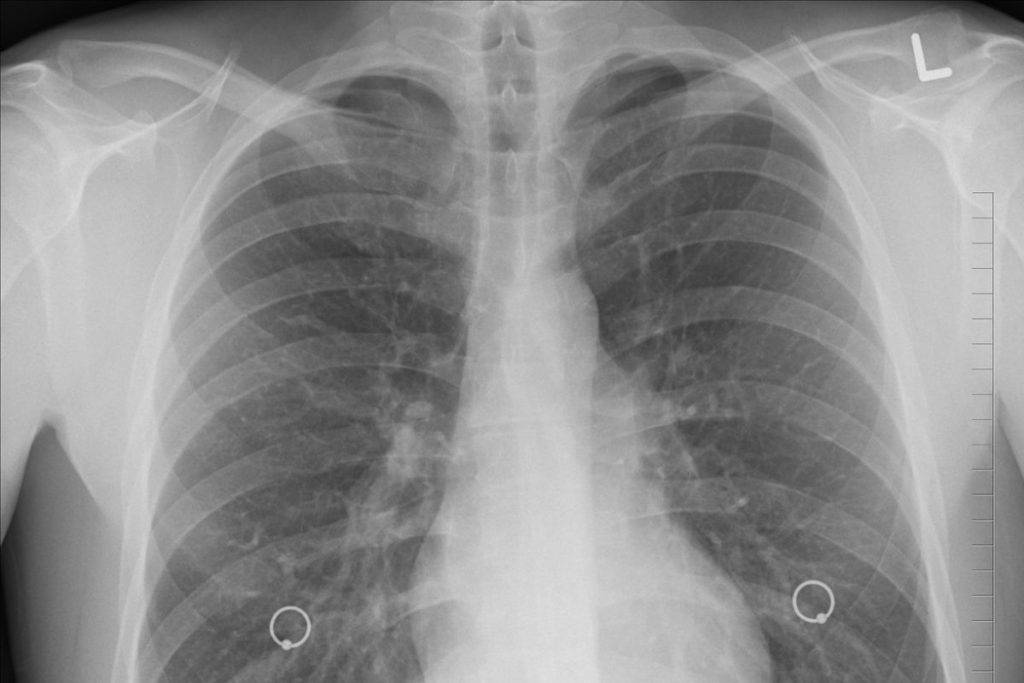

Es sumamente importante que los pacientes post Covid-19 recuperen su capacidad pulmonar y fortalezcan el aparato respiratorio.

De acuerdo con el estado físico de las personas que han padecido Covid-19 se les darán una serie de ejercicios puntuales para rehabilitar sus pulmones.